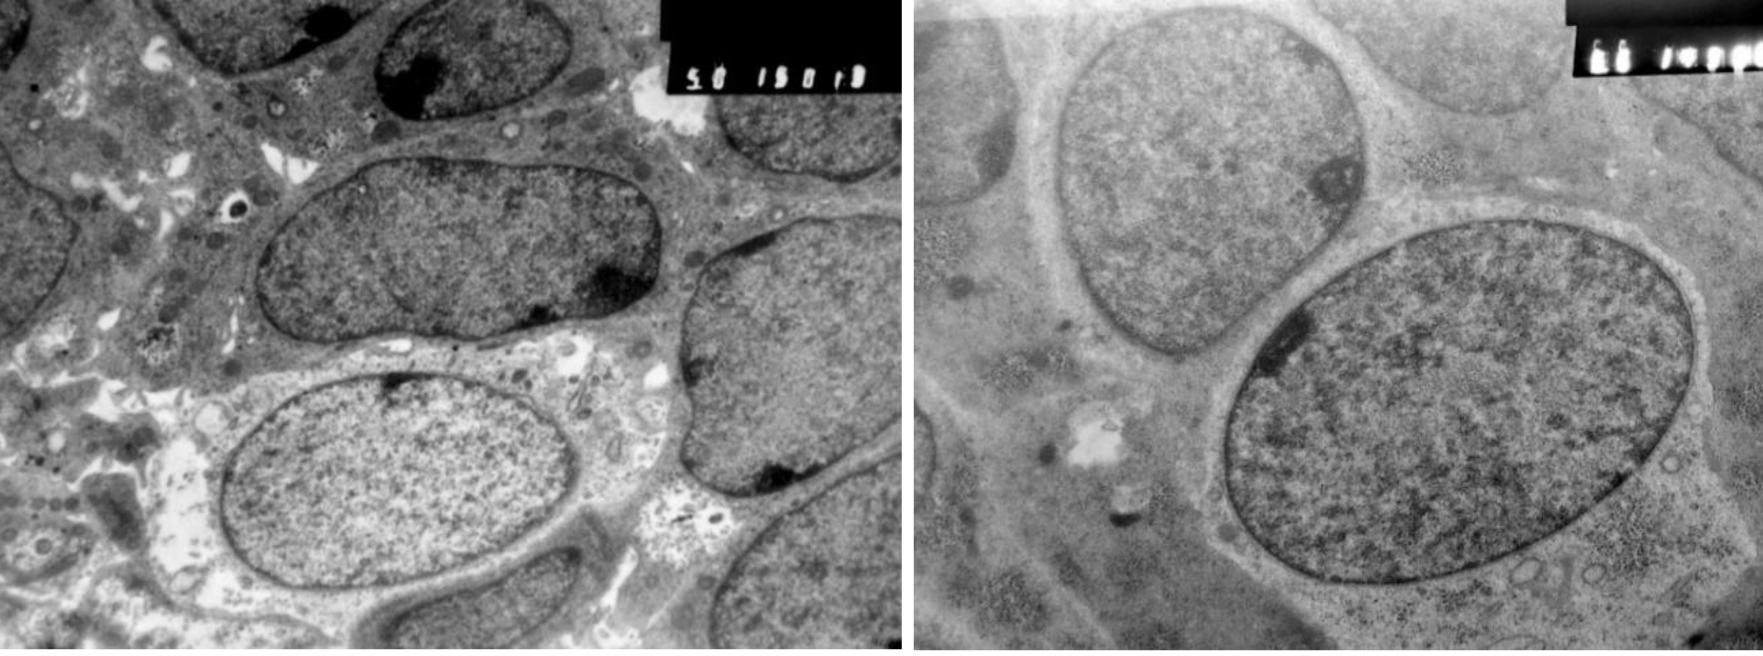

Начиная с 15 СК в эпителии КР выявляются мерцательные клетки и макрофаги моноцитарного генеза. Эпителий преобразуется в полидифферонную структуру. В составе выстилки передней, а затем дна и задней стенки КР, начиная с 19 СК, выявляются дифференцирующиеся аденоциты и аденотропоциты (рис. 5).

Рис. 5. Аденотропоциты в составе эпителия кармана Ратке. Тиреотропоцит (слева), гонадотропоцит (справа). Электроннограмма, ув. ×8000